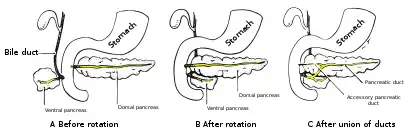

Accessory pancreatic duct

Most people have just one pancreatic duct. However, some have an additional accessory pancreatic duct, also called the Duct of Santorini. An accessory pancreatic duct can be functional or non-functional.[3][4] It may open separately into the second part of the duodenum,[3][4] which is dorsal, and usually (in 70% of people) drains into the duodenum via the minor duodenal papilla. In the other 30% of people, it drains into the main pancreatic duct, which drains into the duodenum via the major duodenal papilla. The main pancreatic duct and the accessory duct both eventually—either directly or indirectly—connect to the second part ('D2', the vertical segment) of the duodenum.

Formation of an accessory pancreatic duct

Formation of an accessory pancreatic duct